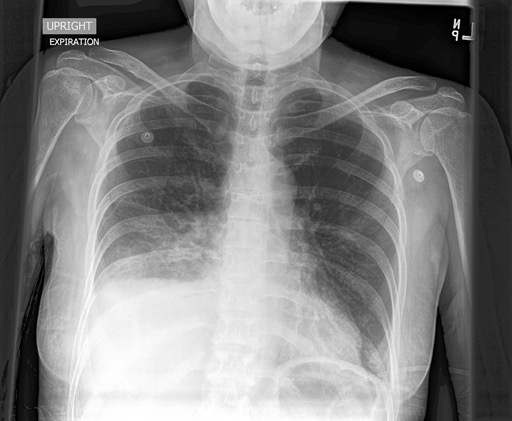

Automated diagnosis prediction from medical images is a valuable resource to support clinical decision-making. However, such systems usually need to be trained on large amounts of annotated data, which often is scarce in the medical domain. Zero-shot methods address this challenge by allowing a flexible adaption to new settings with different clinical findings without relying on labeled data. Further, to integrate automated diagnosis in the clinical workflow, methods should be transparent and explainable, increasing medical professionals' trust and facilitating correctness verification. In this work, we introduce Xplainer, a novel framework for explainable zero-shot diagnosis in the clinical setting. Xplainer adapts the classification-by-description approach of contrastive vision-language models to the multi-label medical diagnosis task. Specifically, instead of directly predicting a diagnosis, we prompt the model to classify the existence of descriptive observations, which a radiologist would look for on an X-Ray scan, and use the descriptor probabilities to estimate the likelihood of a diagnosis. Our model is explainable by design, as the final diagnosis prediction is directly based on the prediction of the underlying descriptors. We evaluate Xplainer on two chest X-ray datasets, CheXpert and ChestX-ray14, and demonstrate its effectiveness in improving the performance and explainability of zero-shot diagnosis. Our results suggest that Xplainer provides a more detailed understanding of the decision-making process and can be a valuable tool for clinical diagnosis.